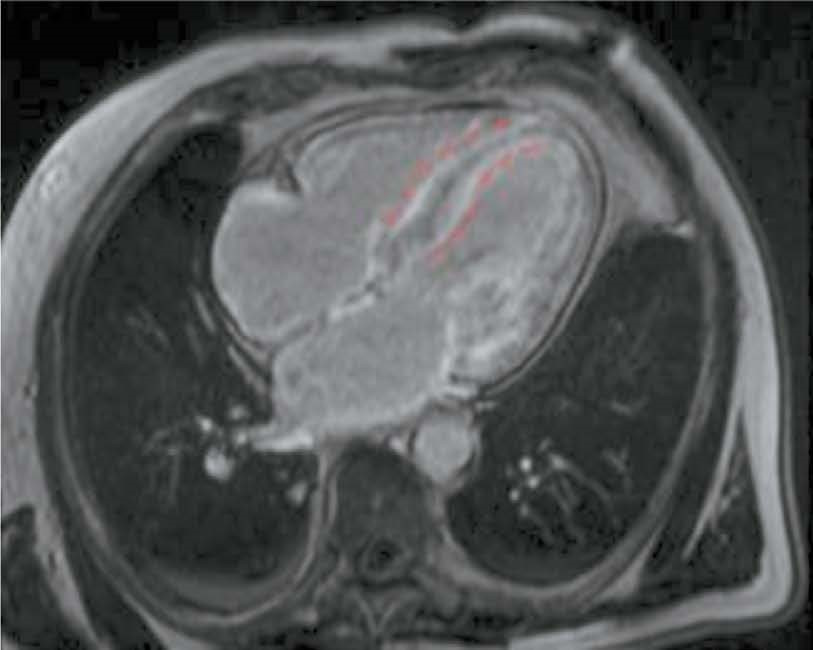

BACKGROUND: The size and location of an infarct lesion and its clear differentiation from normal tissue are important for clinical diagnosis and precision medicine. This paper is based on the study of radiomic attributes for differentiation of infarct and non infarct tissue using non contrast enhanced cine mode cardiac magnetic resonance imaging (MRI) data.

AIM: The aim of the study was to evaluate the potential use and informative value of radiomics analysis to identify post-infarction lesions in the left ventricular myocardium in patients with ischemic cardiomyopathy (ICM) using non-contrast-enhanced cine-mode cardiac MRI.

MATERIALS AND METHODS: Results of contrast-enhanced cardiac MRI were evaluated in 33 patients following surgical treatment for ICM. Texture analysis was performed on 66 lesions in cine-mode cardiac MRI images, and 105 texture attributes were determined for each lesion. Cardiac MRI was performed according to a standard technique using a Vantage Titan 1.5 T MRI scanner (Toshiba). For texture analysis, 3D Slicer version 5.2.2 (Pyradiomics) was used.

RESULTS: During the study, attribute collinearity diagrams were plotted, zero-significance attributes were identified, and attribute significance was determined using a gradient boosting algorithm, and the cumulative significance of attributes was estimated as a function of their total number. By identifying low-significance attributes, the least significant parameters that did not affect the overall significance level were determined. When single-valued attributes were extracted, no corresponding attributes were found. Based on the analysis results, an ROC curve was constructed for Lasso logistic regression (Se=57.14%, Sp=71.43%, AUC=0.76). The main result of this study was to determine radiomic attributes that characterized lesions corresponding to post-infarction cardiosclerosis and intact left ventricular wall based on cine-mode cardiac MRI images.

CONCLUSIONS: This study demonstrated that radiomics analysis of non-contrast-enhanced cine-mode cardiac MRI images is a promising approach to identify lesions corresponding to myocardial infarction and intact wall. This method may potentially be used to identify lesions of post-infarction cardiosclerosis in patients with ICM without contrast enhancement.